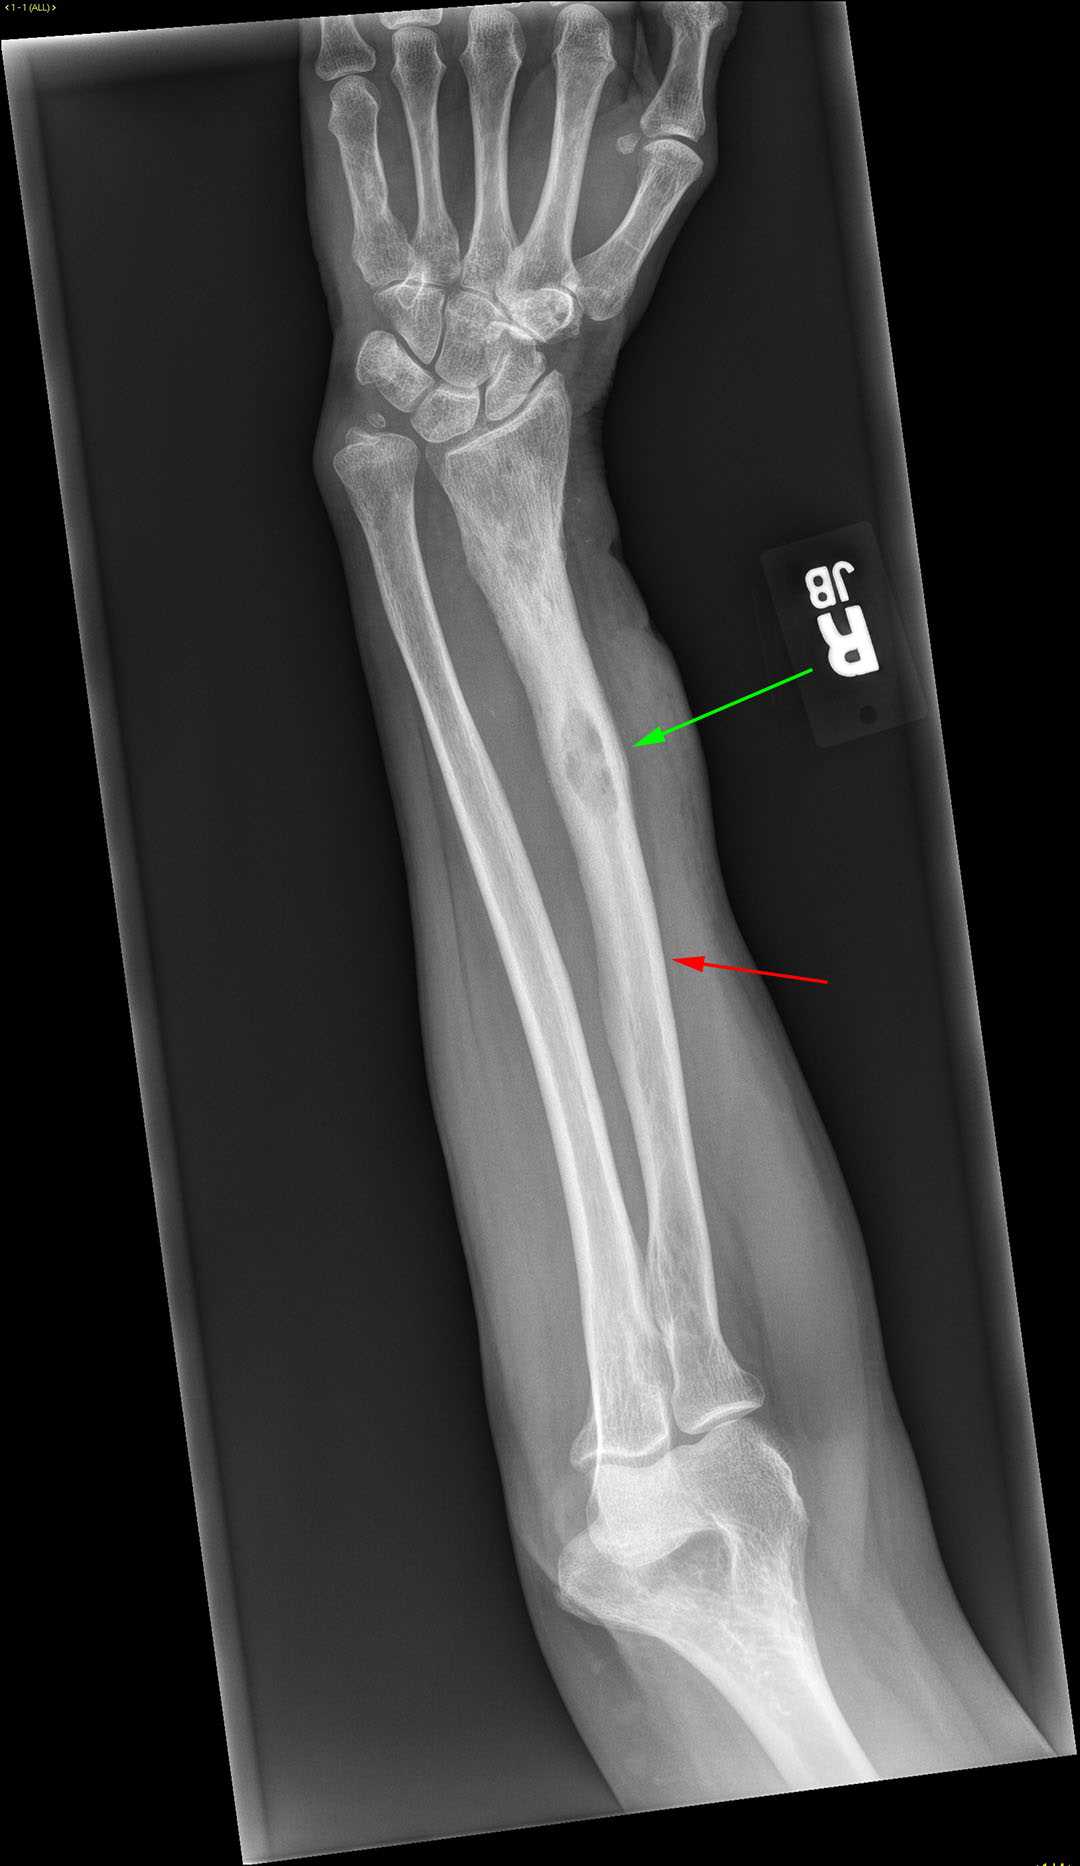

Metastatic thyroid cancer

This is a patient who presented with arm pain. Frontal and lateral radiographs of the humerus were obtained. In the mid diaphysis of the humerus, there is a lytic lesion within the medullary cavity with an associated pathologic fracture as indicated by the red arrows on both radiographs. This lesion has a poorly defined margin but there is no radiographic evidence of a discrete soft tissue mass. In a patient over the age of 40, the leading differential considerations of a lytic lesion with pathologic fracture is metastatic disease and multiple myeloma. The most common cancers which demonstrate lytic osseous metastases include lung, kidney, and thyroid cancers. This patient had a history of follicular thyroid cancer